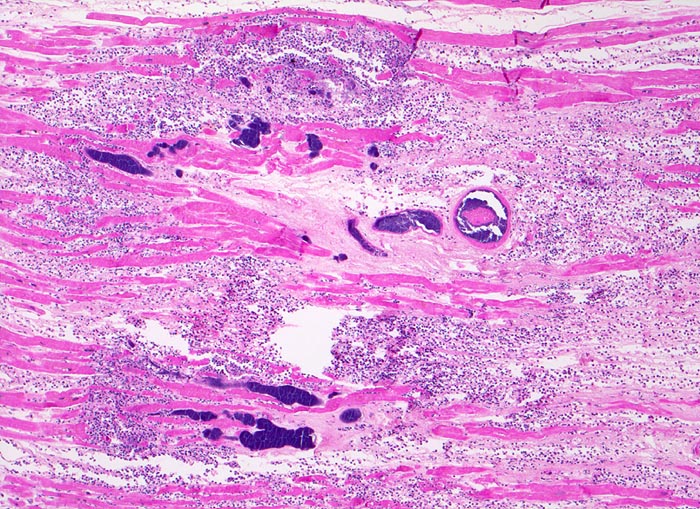

Morphologische Merkmale:

• Blaue Flecken in der Übersicht. Diese entsprechen Ansammlungen von neutrophilen Granulozyten (Mikroabszesse).

• Links unten im Bild sind mehrere Arterien mit intra- und perivaskulären Kokkenbakterien und neutrophilen Granulozyten erkennbar.